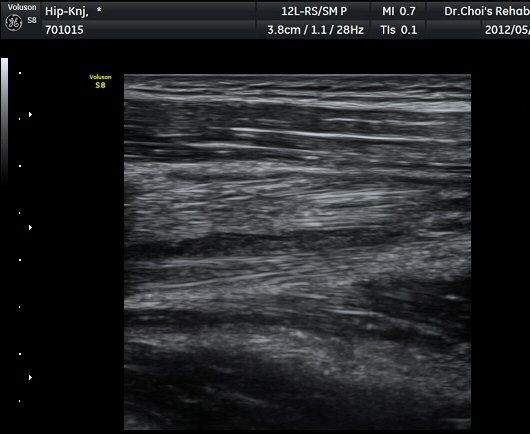

ŽÃËÀÚ¸¦ ¾Æ·¡·Î À̵¿ÇÏ´Ï ´ëÅðÁ÷±Ù³»¿¡ Àú¿¡ÄÚ º¯º¯ÀÌ °üÂûµÈ´Ù(±×¸² 2, 3).